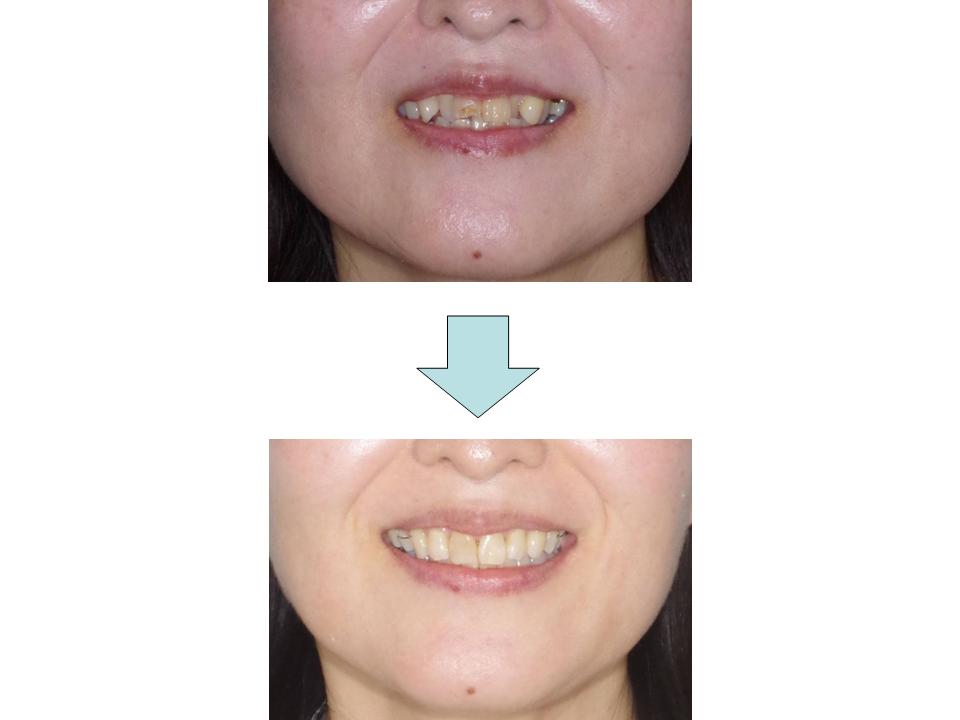

上の前歯が出ている

上の前歯が出ている原因が上下のかみ合わせのズレによるものであるため、上の歯の抜歯を行って前突感の改善を行いました。治療中に妊娠があったためつわりが落ち着いてから装置の撤去を行い、良好なかみ合わせにすることができました。

| 主訴 | 上の前歯が出ている |

| 年齢・性別 | 25歳 / 女性 |

| 抜歯部位 | 上顎両側第一小臼歯、上下顎智歯 |

| 装置 | リンガル(舌側矯正) |

| 期間 | 2年11か月 |